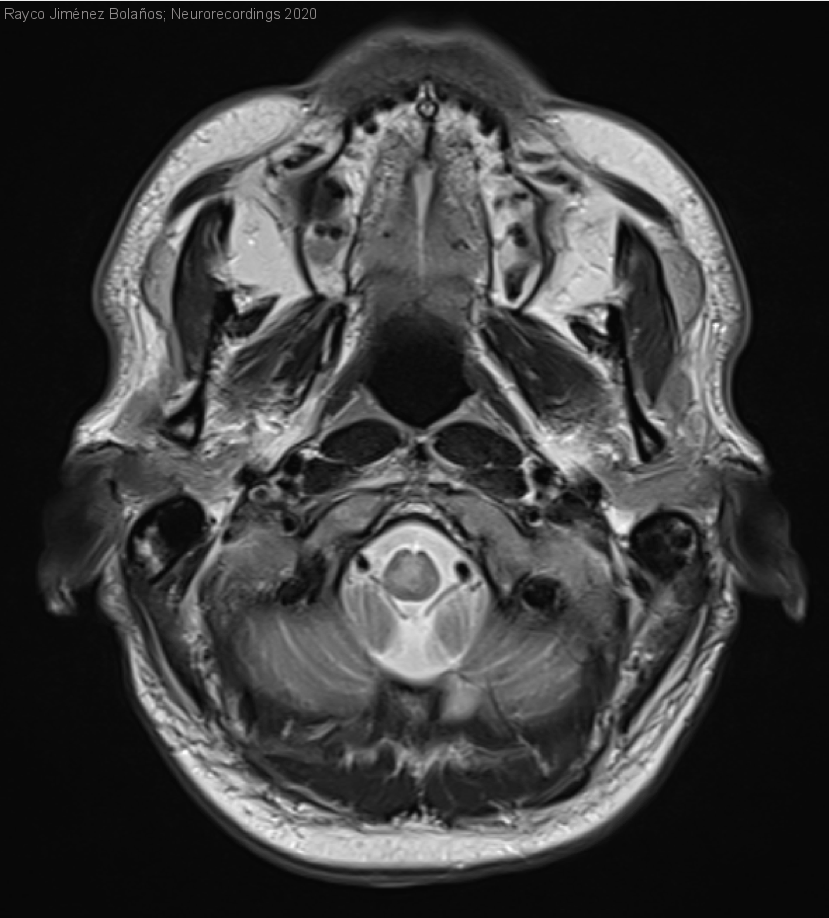

Hombre | 38 años

Diagnóstico final: Esclerosis Múltiple remitente-recurrente

Varón de 38 años con episodios previos de neuralgia del trigémino derecho. Tras esfuerzo físico presenta vértigo, adormecimiento de hemilengua derecha y percepción alterada de los sabores ("tomé una Coca-Cola Light y pensaba que sabía mal, probé la Coca-Cola Zero y...